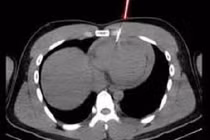

Bệnh nhân được chụp Xquang xương đùi, CT-scan ngực để tầm soát tổn thương ở cơ quan khác, phát hiện vô số nang sán dải còn sống hoặc đã bị hóa vôi “ẩn nấp” trong não, nhu mô phổi, và trong da, cơ trên toàn bộ cơ thể người bệnh.